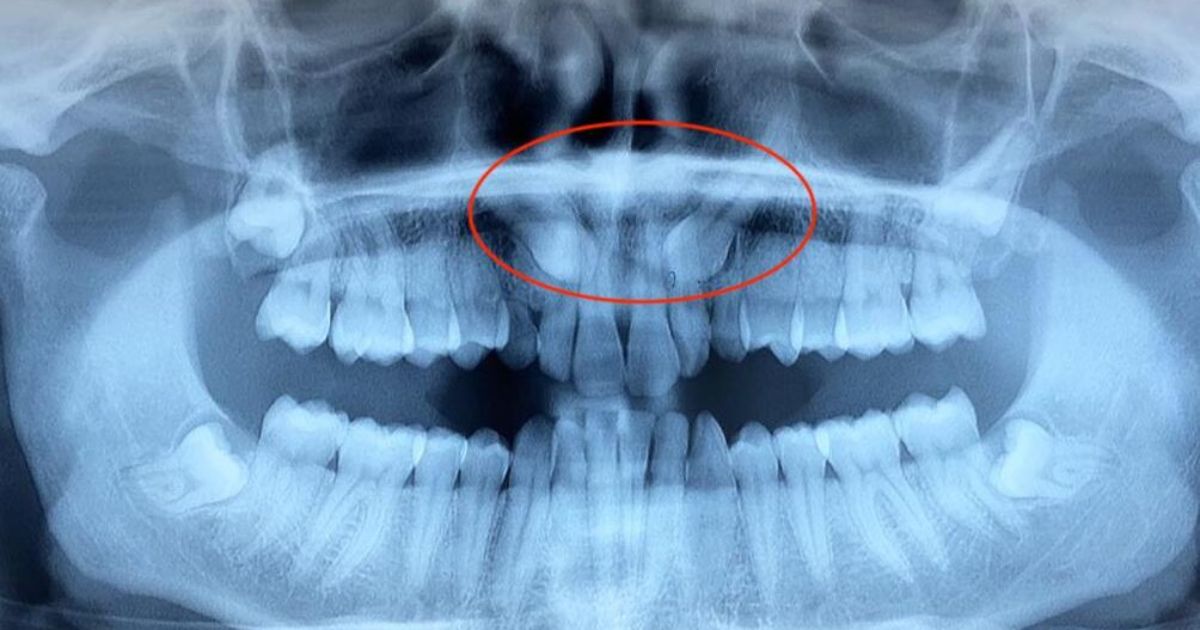

La diagnosi definitiva richiede sempre esami radiografici: una radiografia panoramica (ortopantomografia) permette di visualizzare la presenza del canino incluso, la sua posizione approssimativa e i rapporti con le radici dei denti adiacenti.

In molti casi è necessaria una TAC cone beam (CBCT) per valutare con precisione tridimensionale la posizione del canino, la direzione della corona, l’angolazione e i rapporti con le strutture circostanti, indispensabili per pianificare il trattamento.